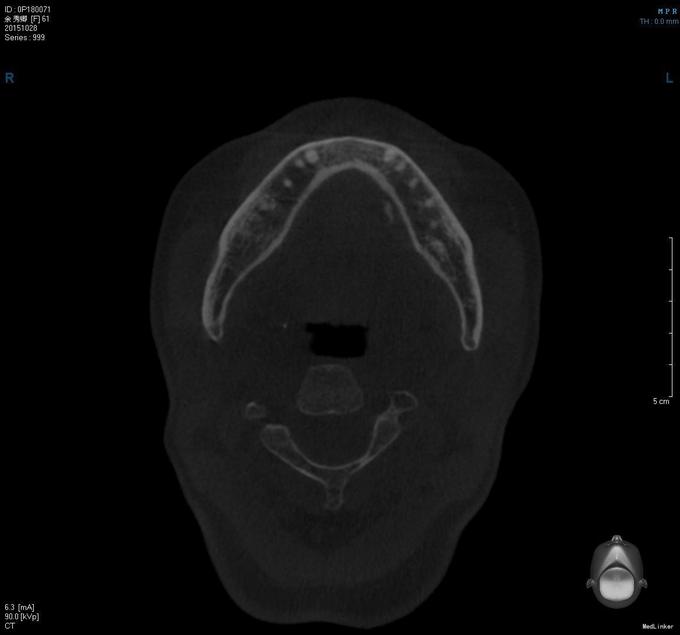

老年女患者,慢性病程。患者于1月前无明显诱因左侧颌下肿痛,呈阵发性针刺样疼痛,伴压痛、耳颞部放射痛,与进食无关,自行消退,患者时而自觉“口咸”,唾液曾有“白色粘稠物”。治疗史自服消炎药,后肿胀感无明显缓解。今为进一步治疗来我院就诊,门诊以"左颌下腺导管结石伴下颌下腺炎"收入院

患者双侧颜面部稍不对称,左侧颌下肿胀,质地软,轻微压痛。双侧TMJ动度基本一致,双侧耳前区无明显压痛。张口度约4.0cm。口内检查:左侧颌下腺导管口黏膜红肿、挤压左颌下腺见导管口清亮液体,双颌诊未触及颌下腺导管硬质物,动度一般,与周围组织无明显粘连。口底唾液量少,余黏膜检查未见明显异常。

出院诊断:1.左侧慢性颌下腺炎2.左颌下腺导管结石,在手术室全麻下行左颌下腺切除术+邻近瓣转移修复术。手术经过顺利,麻醉满意,术后予消炎、消肿等对症治疗。

这个CT显示结石的效果还是比较好的